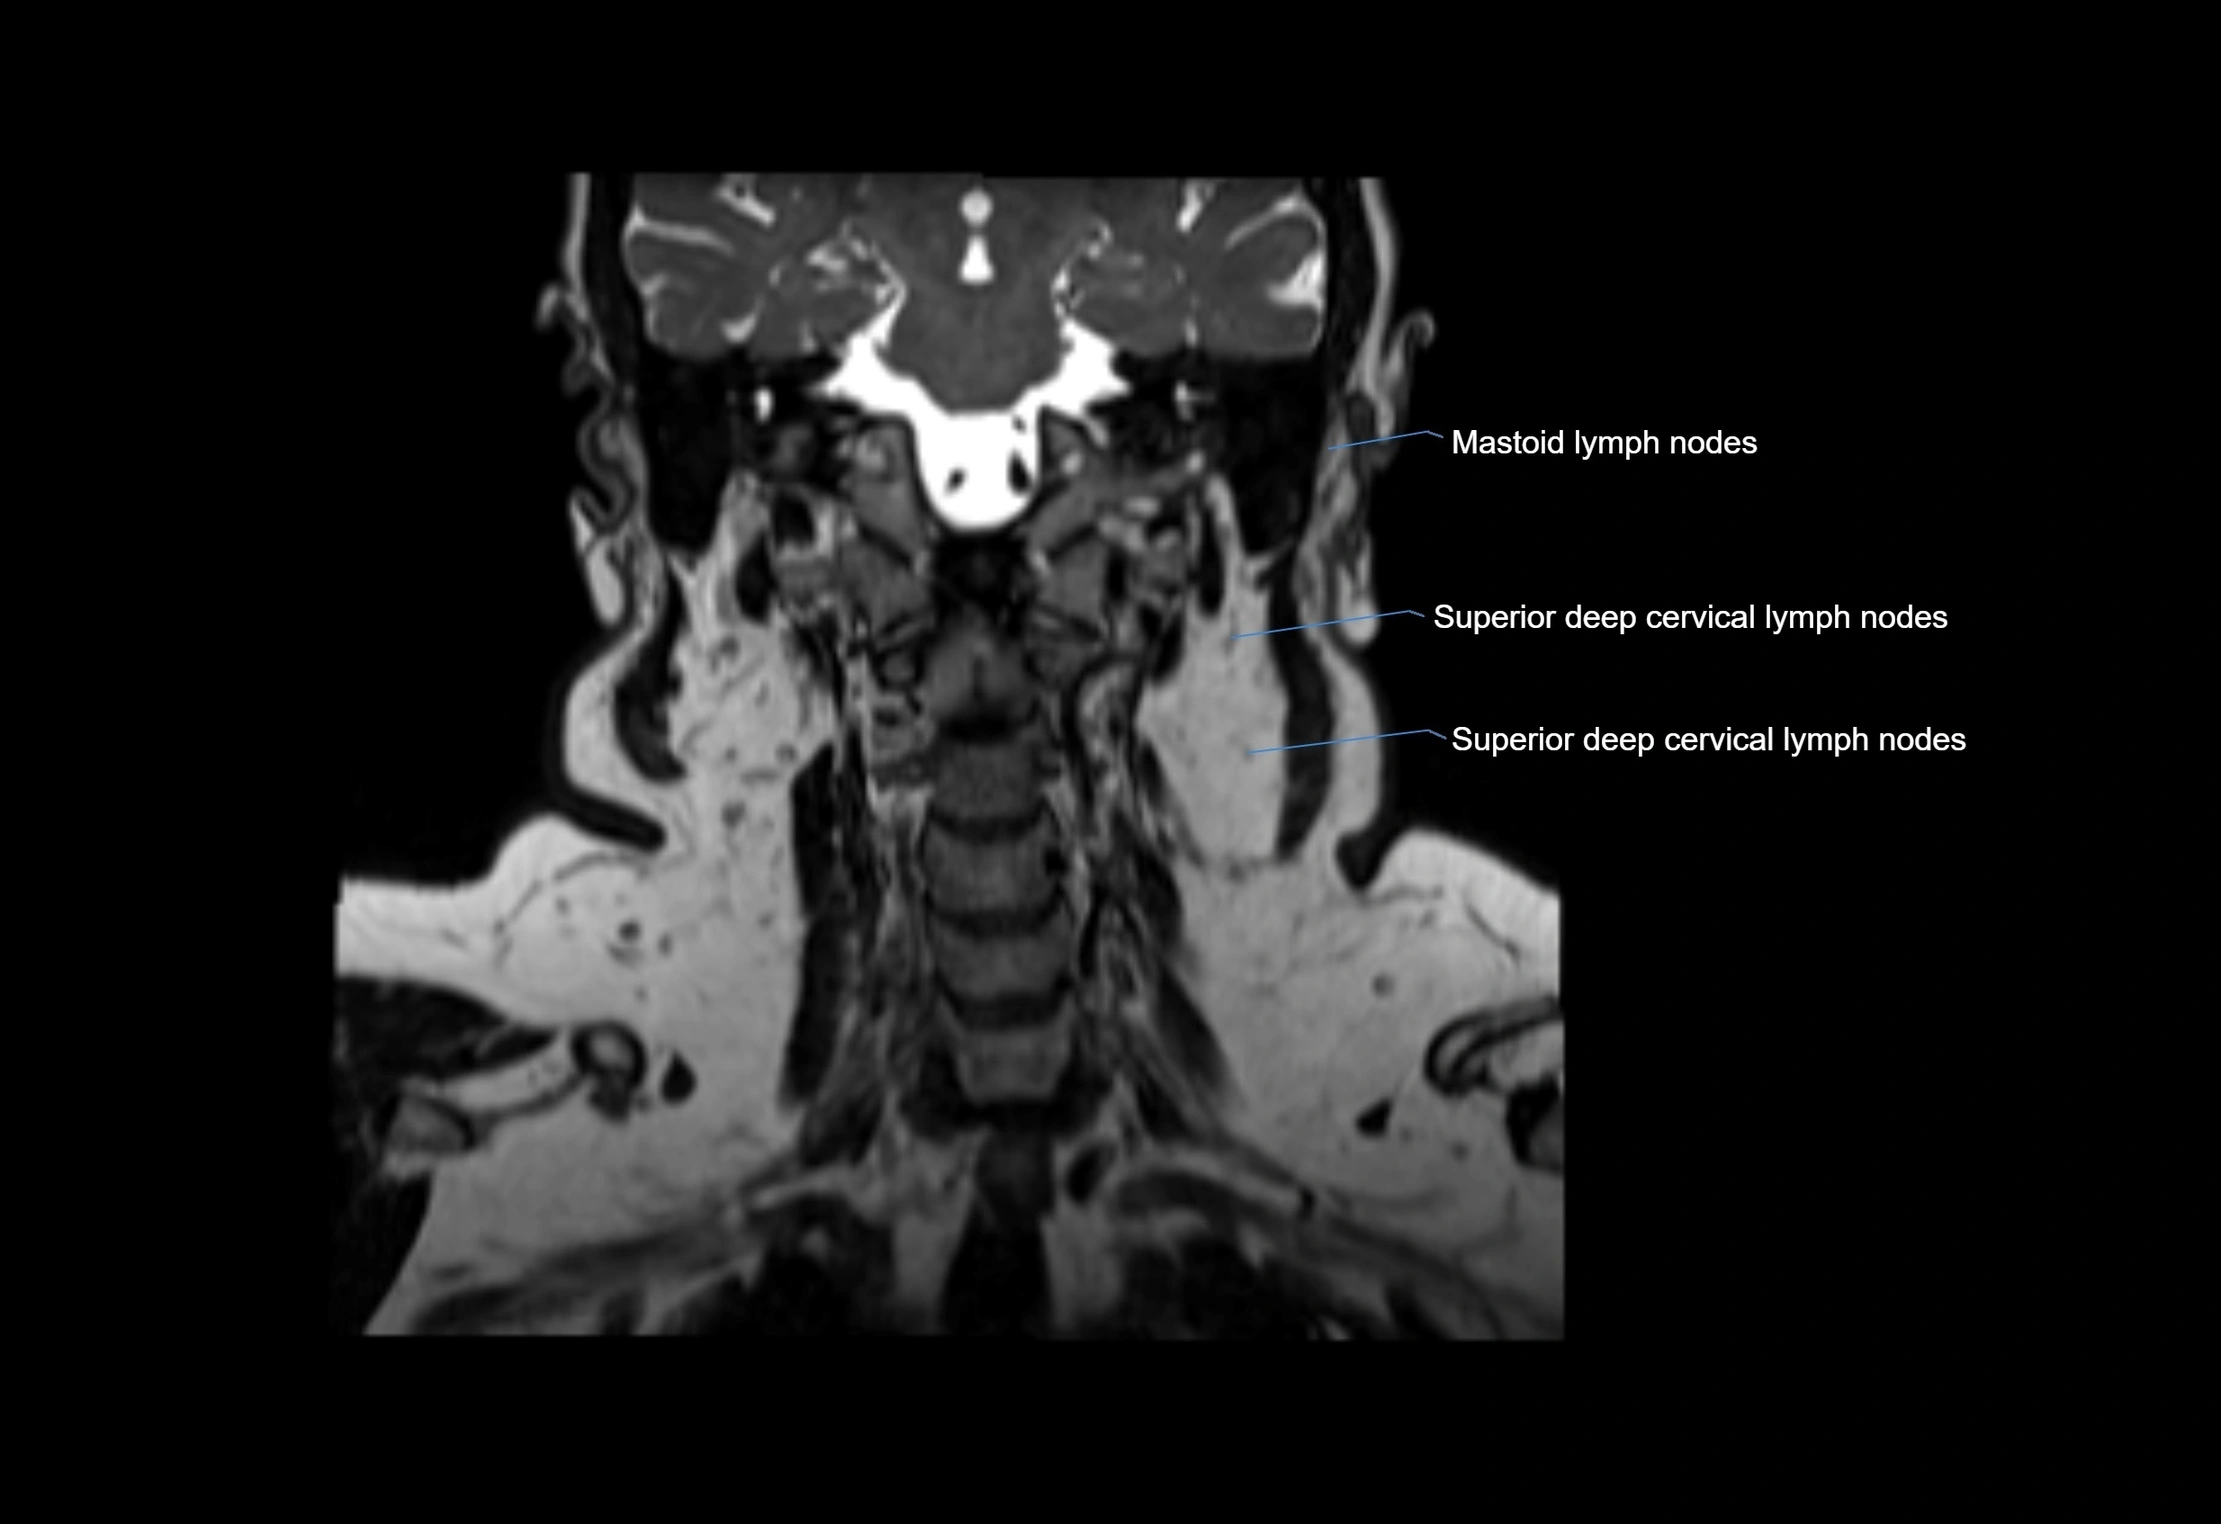

Accessory lymph nodes are small, secondary lymph nodes located along the main facial and cervical lymphatic chains, often adjacent to primary lymph nodes, such as preauricular, submandibular, or occipital nodes. They are typically less than 5 mm in diameter, embedded within subcutaneous fat or connective tissue, and may be variable in number and location. These nodes provide additional filtration and immune surveillance for lymph collected from the face, scalp, and neck regions. Accessory lymph nodes are usually non-palpable in healthy individuals but may enlarge in response to infection, inflammation, or metastasis, making them clinically significant.

Location

• Found along primary lymph node chains, including preauricular, submandibular, parotid, and occipital regions

• Embedded in subcutaneous fat or superficial fascia, often lateral or posterior to primary nodes

• Variable in number; may occur unilaterally or bilaterally, depending on individual anatomy

MRI Appearance

T2-weighted images:

• Nodes show intermediate signal, with surrounding fat bright

• Useful for detecting edema, inflammation, or infiltration

• Fatty hilum may appear slightly hyperintense relative to cortex

MRI images

image